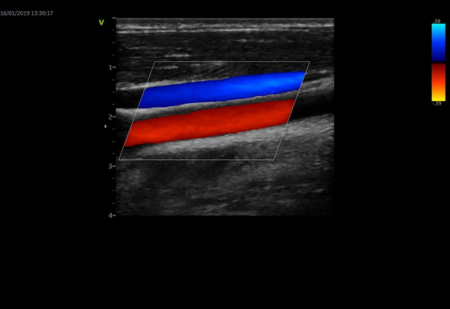

B-Flow недопплеровская визуализация кровотока в сосудах

• Поддержка режимов исследования: 2D, ЦДК, спектральный допплер, тканевой спектральный и цветовой допплер